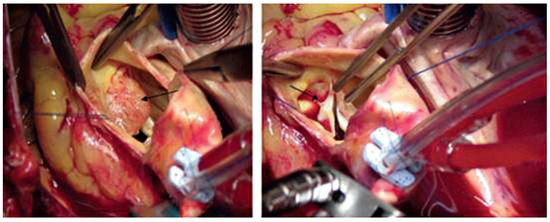

A patient with Morbus Behçet was admitted with severe symptomatic aortic regurgitation caused by aortitis that mimicked infective endocarditis. After aortic valve replacement and antibiotic treatment, regurgitation and systemic inflammation recurred....